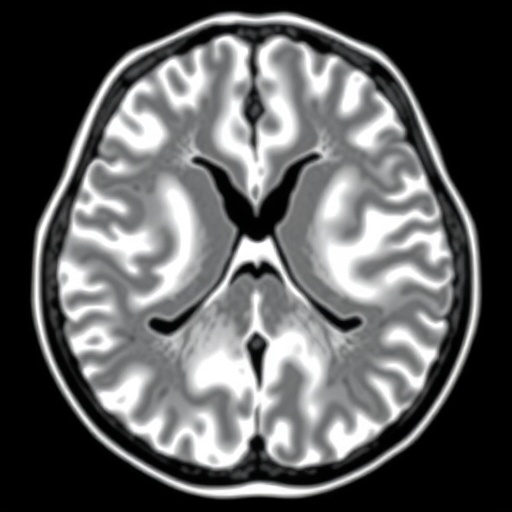

Hepatocellular carcinoma, the most common primary liver malignancy, often presents complex challenges due to its heterogeneous nature and variable response to conventional therapies like TACE. While TACE remains a stalwart intervention for intermediate-stage HCC, inconsistent treatment outcomes impede optimized clinical management. This newly developed algorithm addresses this critical gap by harnessing pretreatment magnetic resonance imaging (MRI) scans to forecast objective response to initial TACE, potentially sparing patients from ineffective interventions.

The research leverages retrospective datasets collated from three distinct medical institutions, encompassing a diverse cohort of HCC patients treated with TACE. Central to this effort is the creation of a deep learning framework, designated DLTR, that was meticulously compared against various competing algorithms to ascertain superior predictive performance. Building upon these foundations, the scientists incorporated a multilayer perceptron model, producing an enhanced classifier termed DLTR_MLP, which synergistically fuses imaging-derived features with pivotal clinical parameters.